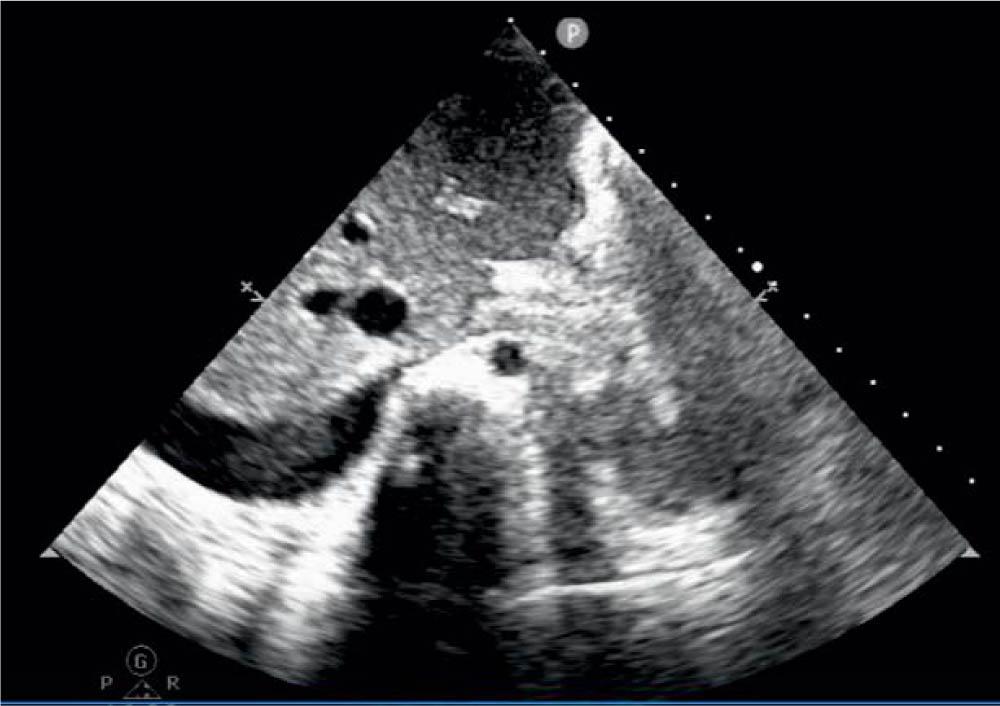

The electrocardiogram was normal. Repeated transthoracic echocardiography confirmed the moderate-severe systolic dysfunction (LVEF = 30–40%), the thin layer of pericardial effusion, a right pleural effusion of about 16 mm, Figure 1, mild mitral regurgitation, Figure 2, initial normal coronary artery diameter, but in evolution, in the fifth day dilated coronary arteries were noticed - the left main coronary artery measured 3.4 mm (Z-score = 2.8), the left anterior descending coronary artery measured 2.5 mm (Z-score = 2.6), and the right coronary artery was of normal size 2 mm (Z-score = 0.6) (Figure 3).

Figure 1

Right pleural effusion.